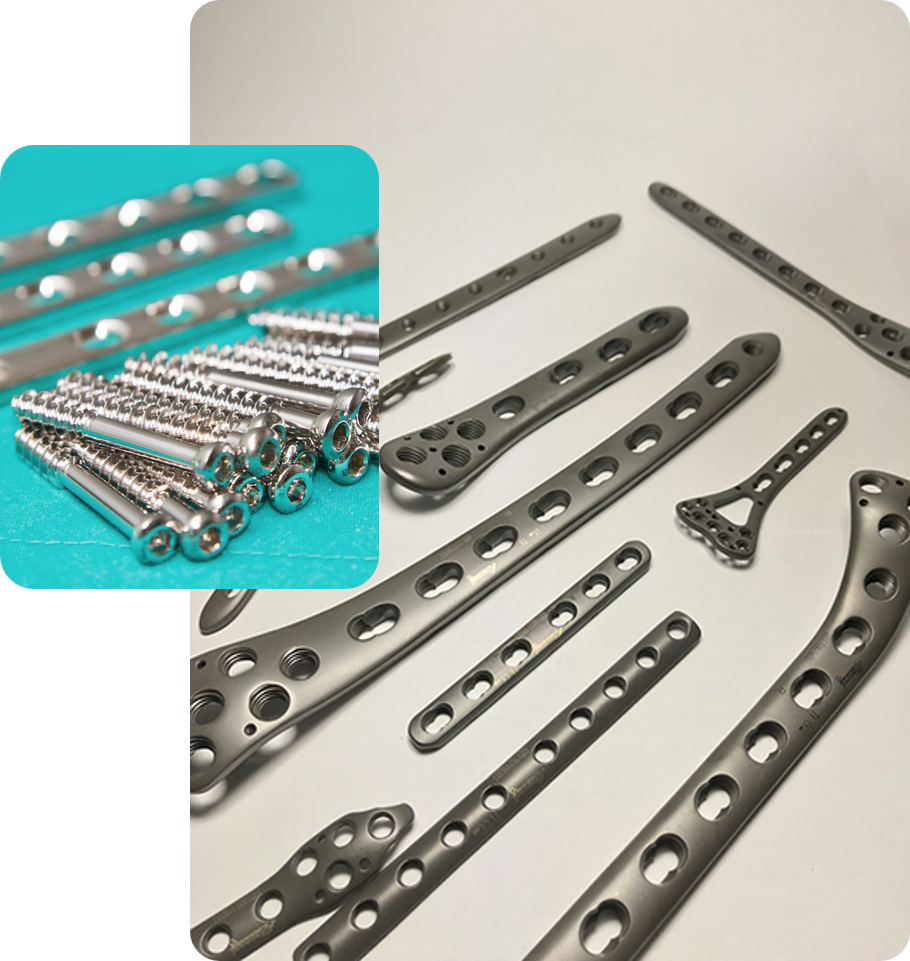

Somos una empresa dedicada a la comercialización y distribución de material y equipos y/o dispositivos médicos

Brindamos soluciones costo efectivas que permiten a los médicos y a los centros de salud implementar elementos de calidad que garanticen el éxito de los procedimientos realizados con el principal objetivo de proteger la vida de los pacientes